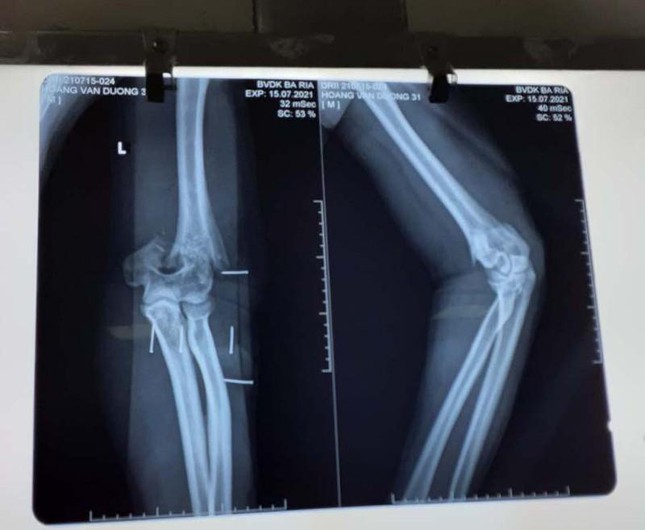

Hình chụp phim thương tích ở cánh tay của thượng úy Hoàng Văn Dương. Ảnh: BV.

Trong khi đó, bác sĩ CKI Lại Thế Sở, khoa Ngoại Chấn thương Chỉnh hình, Bệnh viện Bà Rịa, tỉnh Bà Rịa-Vũng Tàu cho biết, bác sĩ tiến hành phẫu thuật cho thượng úy Dương. Tình trạng vết thương của bệnh nhân trước khi mổ là bị cắt đứt phần gân cơ, phần mềm phía sau khuỷu tay, chém gãy lìa đầu dưới xương cánh tay.

Các bác sĩ đã phẫu thuật kết hợp xương và khâu nối các cấu trúc bị tổn thương. Sau khi mổ gắn lại xương. Ca mổ tiến hành trong 3h. Hiện tại, sức khỏe của thượng úy Dương ổn định, chờ thời gian phục hồi các tổn thương. Sau này khả năng phục hồi vận động tốt.